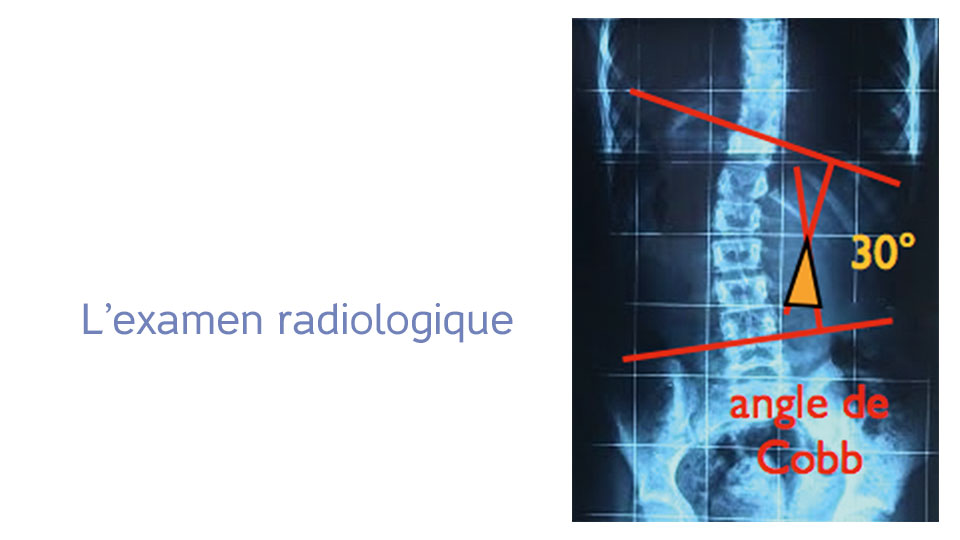

Cobb (angle de) :

angle formé par les 2 parallèles aux plateaux des vertèbres les plus inclinées sur l’horizontal aux extrémités de la courbure scoliotique.